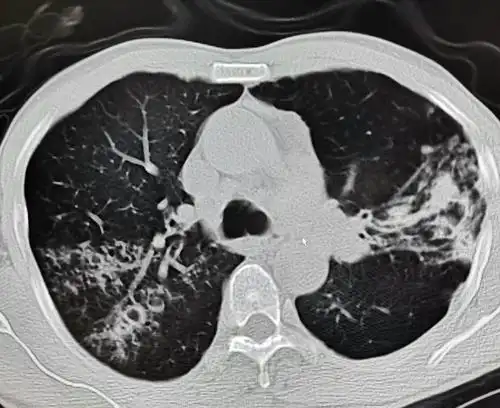

支气管扩张症ct表现 柱状支气管扩张:呈管状,环状及椭 圆形阴影

ct显示肺部支气管扩张伴感染

支气管扩张影像表现特点